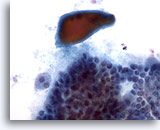

Negatief voor maligne cellen consistent met Hashimoto-thyroïditis

Wij zijn er achter gekomen dat ThinPrep niet optimaal is voor de diagnose van thyroïditis.[6] Hashimoto-thyroïditis wordt gekenmerkt door lagen of groepen folliculaire cellen met variërende mate van Hürthle-celveranderingen op een achtergrond van variërende aantallen lymfocyten en plasmacellen met incidenteel lymfoïde en folliculaire kernaggregaten. Omdat lymfocytisch/Hashimoto-thyroïditis een veelvoorkomende bevinding is bij de schildklier, is de monsterverzameling essentieel bij het uitsluiten van andere eveneens voorkomende en meer belangrijke laesies.